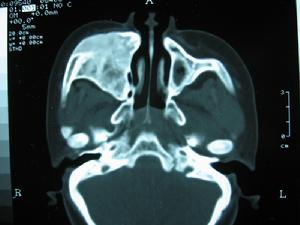

X線鼻竇拍片顯示鼻竇黏膜增厚或有液平面,有血腫者可見半圓形陰影。

症狀發生在飛機下降過程中或下降後發生。主要為額部疼痛或面頰及磨牙麻木,間或有鼻衄,偶有發生休克者。鼻內分泌物呈粘液性,常帶血絲。鼻腔檢查常為原有病變所掩蓋,或未發現異常,中鼻道內可見血性分泌物。X線照片竇內黏膜增厚,竇腔混濁,常有液平面,有黏膜下血腫時則可見半圓形影。輕者數小時或數日可逐漸恢復,重者常遷延數周方可治癒。合併化膿性感染者症狀加重,時間亦久,並伴發熱。

主要為前額或頰部不同程度脹痛,伴上列牙根疼痛,偶有鼻出血、眼痛、流淚及視力模糊等。鼻鏡檢查可見黏膜充血和漿液血性分泌物,竇口附近黏膜腫脹或息肉等。X線鼻竇拍片顯示鼻竇黏膜增厚或有液平面,有血腫者可見半圓形陰影。